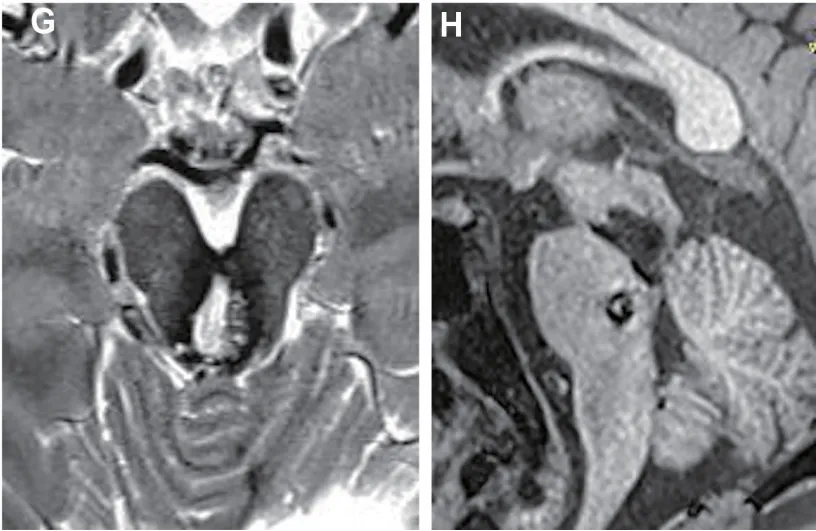

患者术后接受系统化、阶段性的康复治疗,从床旁被动活动开始,逐步过渡到坐起、站立训练。术后5个月进行磁共振成像复查,影像学证据证实中脑海绵状畸形(MCM)完全切除,卫星病灶大小保持稳定且无出血征象。神经功能恢复呈现缓慢但持续改善的良好趋势。